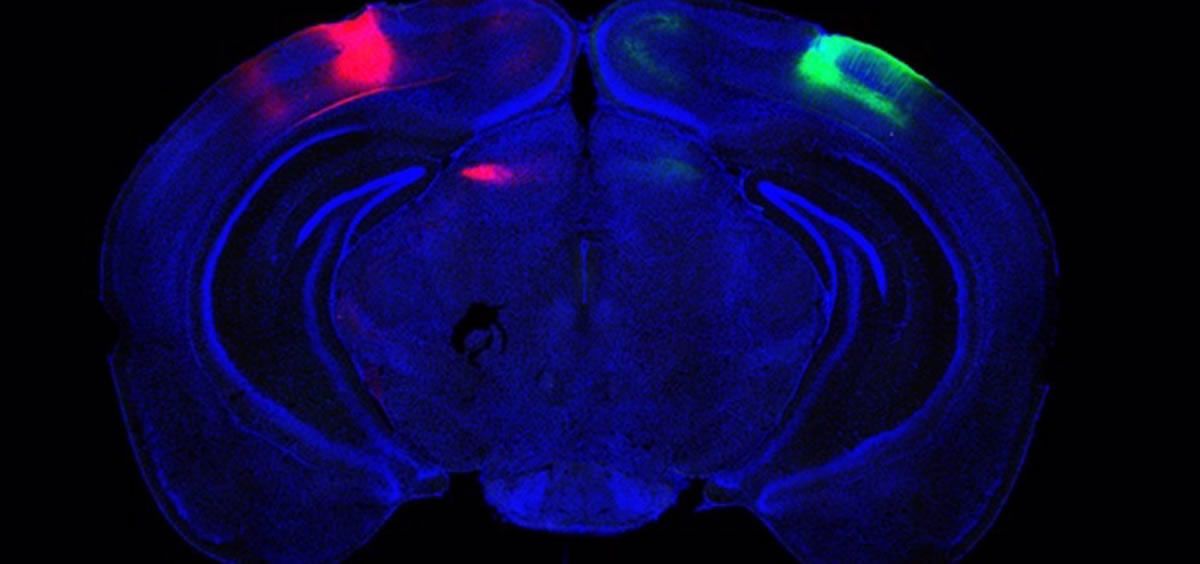

En el estudio, Adaikkan, Tsai, Thomas McHugh y sus coautores descubrieron y rastrearon las neuronas de V1 que extendían sus axones por todo el cuerpo calloso, que conecta los hemisferios cerebrales, hasta las células de V1 del otro lado del cerebro. Allí, descubrieron que las neuronas transhemisféricas (CH) forjaban conexiones, o sinapsis, con las células objetivo, proporcionándoles una estimulación "excitatoria" para impulsar su actividad. Adaikkan también descubrió que las neuronas CH eran mucho más propensas a activarse en una tarea de discriminación de novedades que las neuronas V1 en general o las neuronas de otras regiones muy implicadas en la memoria, como el hipocampo o el córtex prefrontal.

Descubrieron que la inhibición química de las células CH interrumpía la sincronía del ritmo entre las V1, lo que reflejaba las medidas realizadas en ratones modelo de alzhéimer. Además, la interrupción de la actividad de las células CH socavaba la capacidad de discriminación de novedades. Para comprobar si la naturaleza transhemisférica de las células era lo que importaba específicamente, diseñaron las células CH para que se pudieran controlar con destellos de luz (una tecnología denominada optogenética). Cuando hicieron brillar la luz sobre las conexiones que forjaron en el otro hemisferio para inhibirlas, descubrieron que al hacerlo se comprometía de nuevo la capacidad de discriminación visual.